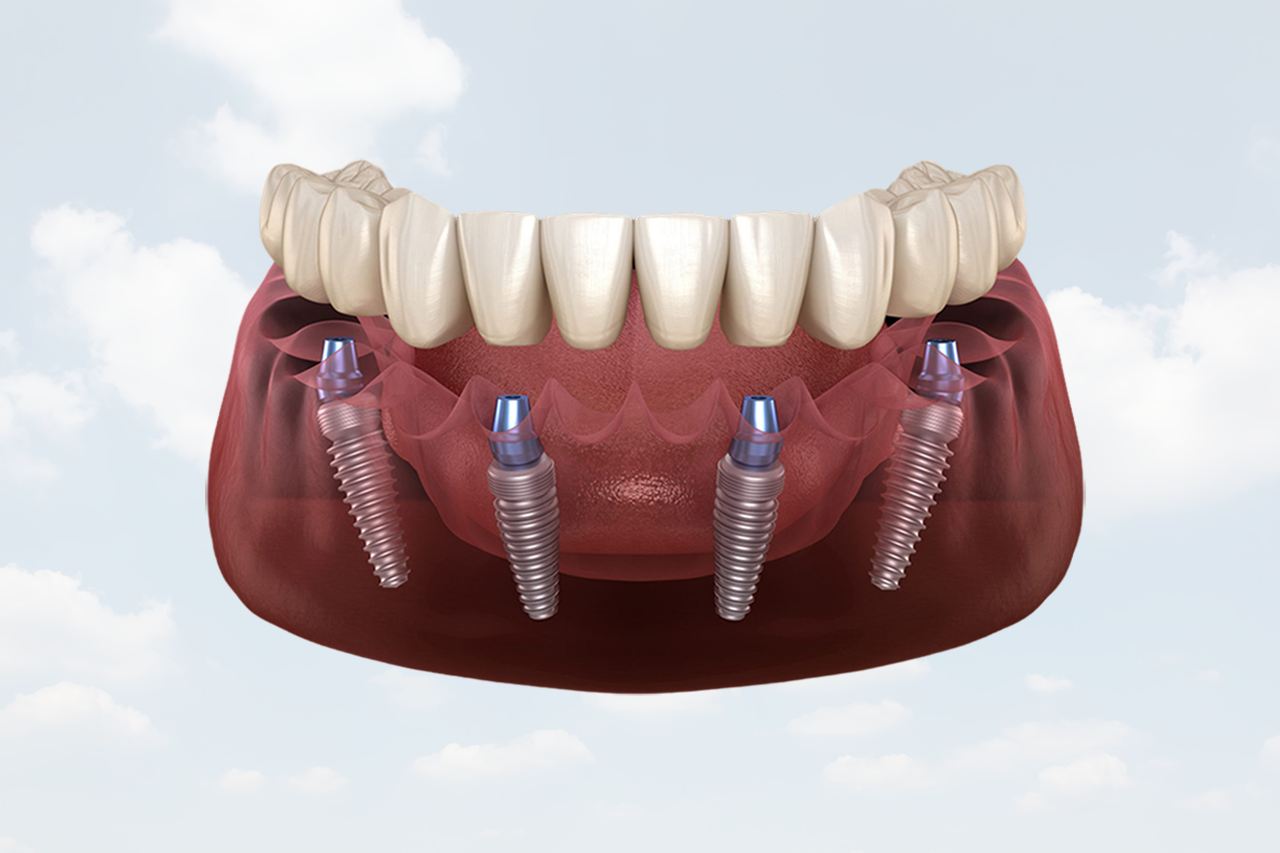

Permanent solution for missing teeth

Full arch fixed teeth